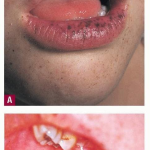

PJS is an autosomal dominant cancer predisposition syndrome first described by Peutz (1921) and Jeghers (1949). Mucocutaneous pigmentation and intestinal hamartomatous polyposis are hallmarks of the disease . The pigmentary lesions resemble those of Carney complex, with small hyperpigmented macules typically appearing in childhood (not present at birth) on the lips and buccal mucosa but they may also involve the eyelids, hands, and feet. The most common malignancies associated with PJS are gastrointestinal (small intestine, colorectal, stomach, pancreas). In addition, nongastrointestinal neoplasms such as breast, cervix, and endocrine tumors (thyroid, testicular, ovarian) have been described. More than one-half of all cases of PJS can be attributed to a mutation in the serine/threonine kinase 11 (STK 11 or LKB 1) gene, which is therefore thought to act as a tumor suppressor gene. Close surveillance of PJS patients from a young age is warranted. For Bannayan-Riley-Ruvalcaba syndrome, see on-line version